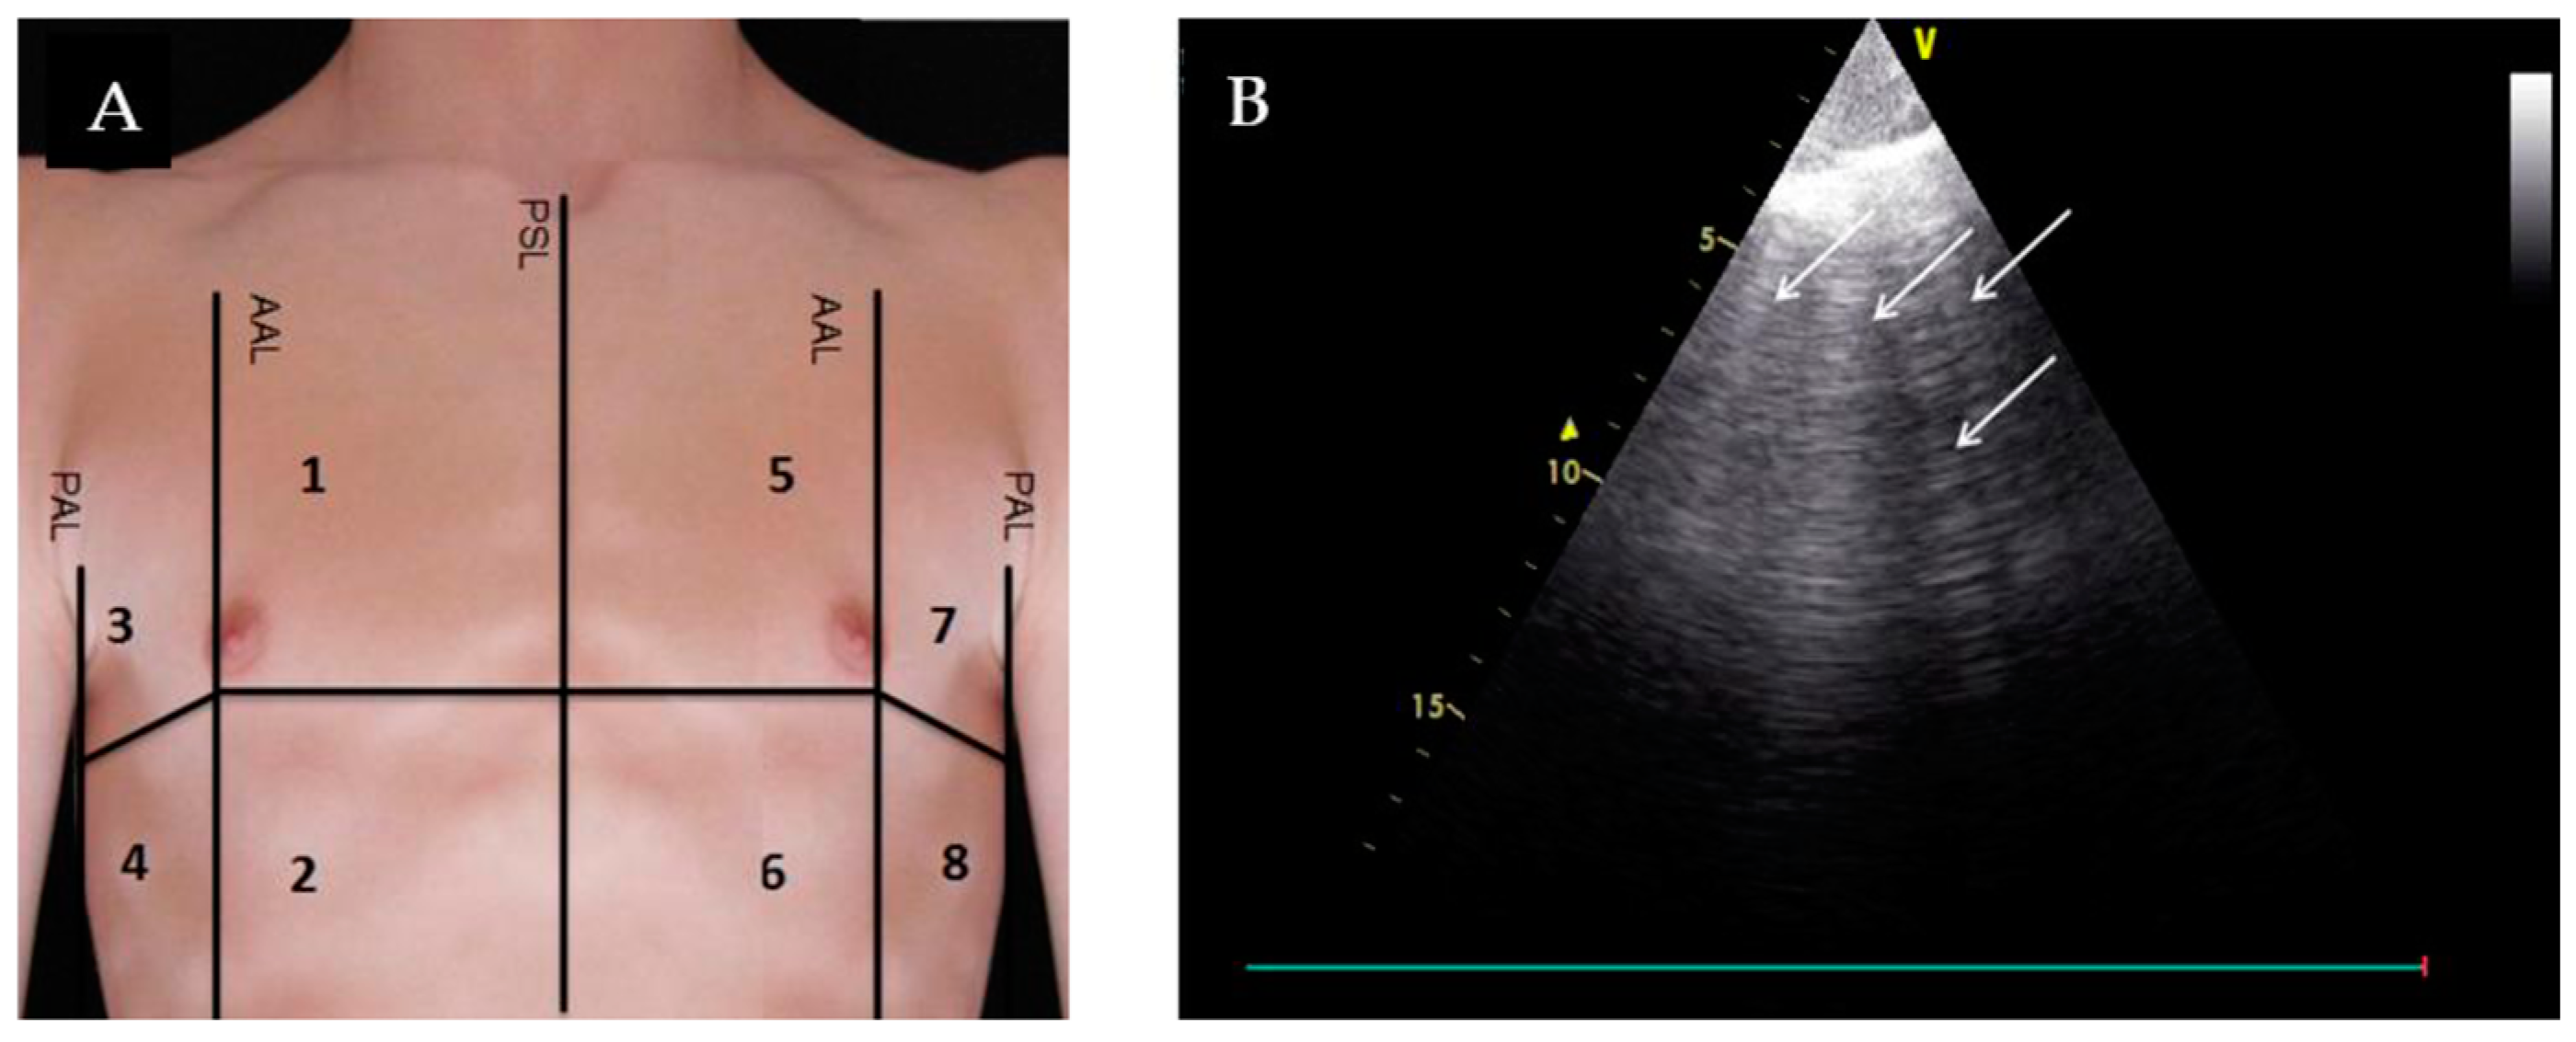

3. Lung Ultrasound (LUS)

- Maw, A.M.; Hassanin, A.; Ho, P.M.; McInnes, M.D.F.; Moss, A.; Juarez-Colunga, E.; Soni, N.J.; Miglioranza, M.H.; Platz, E.; DeSanto, K.; et al. Diagnostic Accuracy of Point-of-Care Lung Ultrasonography and Chest Radiography in Adults With Symptoms Suggestive of Acute Decompensated Heart Failure: A Systematic Review and Meta-analysis. JAMA Netw. Open 2019, 2, e190703. [Google Scholar] [CrossRef] [PubMed]

- Glockner, E.; Wening, F.; Christ, M.; Dechene, A.; Singler, K. Lung Ultrasound Eight-Point Method in Diagnosing Acute Heart Failure in Emergency Patients with Acute Dyspnea: Diagnostic Accuracy and 72 h Monitoring. Medicina 2020, 56, 379. [Google Scholar] [CrossRef] [PubMed]

| Lichtenstein et al., 2009 [10] | Prospective observational | Lung US | Mechanically ventilated ICU patients | Association between A-line pattern and PCWP | n = 102 | A-line predominant lung pattern had 90% specificity, 67% sensitivity, 91% positive predictive value, and 65% negative predictive value for diagnosing a PCWP ≤13 mm Hg. |

| Imanishi et al., 2022 [11] | Prospective cohort | 8-zone lung US | Acute HF patients | Association between B-line pattern and PCWP | n = 116 | 1. Clear transition point where PCWP correlated with sudden increase in B-lines: HFrEF, at PCWP = 25 (Δ of 23 B-lines); HFpEF, at PCWP = 19 (Δ of 8 B-lines). 2. Greater than 6 B-lines at discharge resulted in higher risk for cardiac events (HR 12.6, 95% CI: 4.71–33.7; log-rank, p < 0.0001). |

| Coiro et al., 2015 [12] | Prospective cohort | 28-zone lung US at discharge | Acute HF patients | Association between B-line pattern and event free survival (all-cause death or HF hospitalization) | n = 60 | Three-month event-free survival: 27 ± 10% in patients with ≥30 B-lines and 88% ± 5% in those with < 30 B-lines (p < 0.0001). |

| Dubón-Peralta et al., 2022 [13] | Systematic review | Lung US | Acute HF patients | Association between B-line number and hospital readmission/mortality | 14 studies | 1. More than 30–40 B-lines at admission were a risk factor for readmission or mortality. 2. Persistent B-lines >15 was also a risk factor for readmission or mortality. |

| Mhanna et al., 2022 [14] | Systematic review and meta-analysis | Lung US-guided diuresis | Outpatient HF patients | HF hospitalization rates and all-cause mortality in HF patients undergoing LUS-guided diuresis vs. standard of care | 493 patients across three studies | No significant difference in the rates of heart failure hospitalization between the two groups (RR 0.65; 95% CI 0.34–1.22; p = 0.18). No significant difference in all-cause mortality (RR 1.39; 95% CI 0.68–2.82; p = 0.37). |

| Li et al., 2022 [15] | Meta analysis | Lung US-guided diuresis | Outpatient HF patients | Effect of LUS-guided treatment vs. usual care in reducing the major adverse cardiac event (MACE) rate in patients with HF | 1203 patients over ten RCT studies | LUS-guided treatment group was associated with a significantly lower risk of MACE compared to standard of care (RR, 0.59; 95% CI: 0.48–0.71; p < 0.001). |

| Lung Ultrasound | ||||

| Evaluation for B-lines | Absence of B-lines |

|

| |